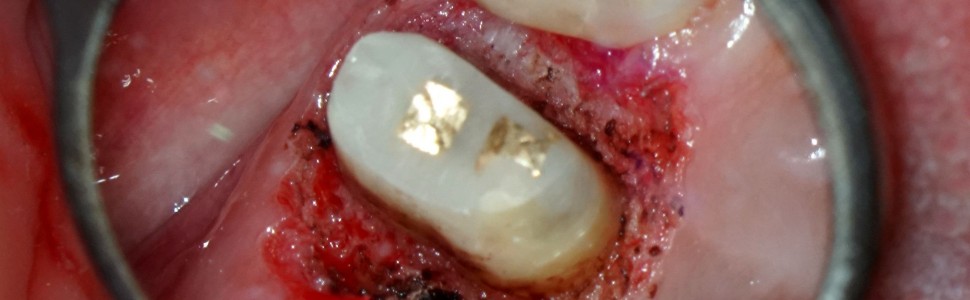

Opis przypadku leczenia zęba 24 ze znaczną utratą tkanek twardych, próchnicą poddziąsłową i nieszczelnością rozległej odbudowy kompozytowej z wykorzystaniem lasera Er:YAG, lasera Nd:YAG, druku 3D oraz techniki szlifu bezstopniowego, mający na celu zobrazowanie, w jaki sposób łącząc wykorzystanie nowoczesnych urządzeń oraz zachowawcze podejście można przeprowadzić nawet najbardziej skomplikowane procedury odtwórcze przewidywalnie, bezpiecznie i szybko.

Case report of tooth treatment 24 with significant loss of hard tissues, subgingival caries and leakage of extensive composite reconstruction, using the Er: YAG laser, Nd: YAG laser, 3D printing and vertipreop technique, aimed at illustrating how with the combination of the use of modern devices and conservative approach even the most complex restoration procedures, can be carried out predictably, safely and quickly.